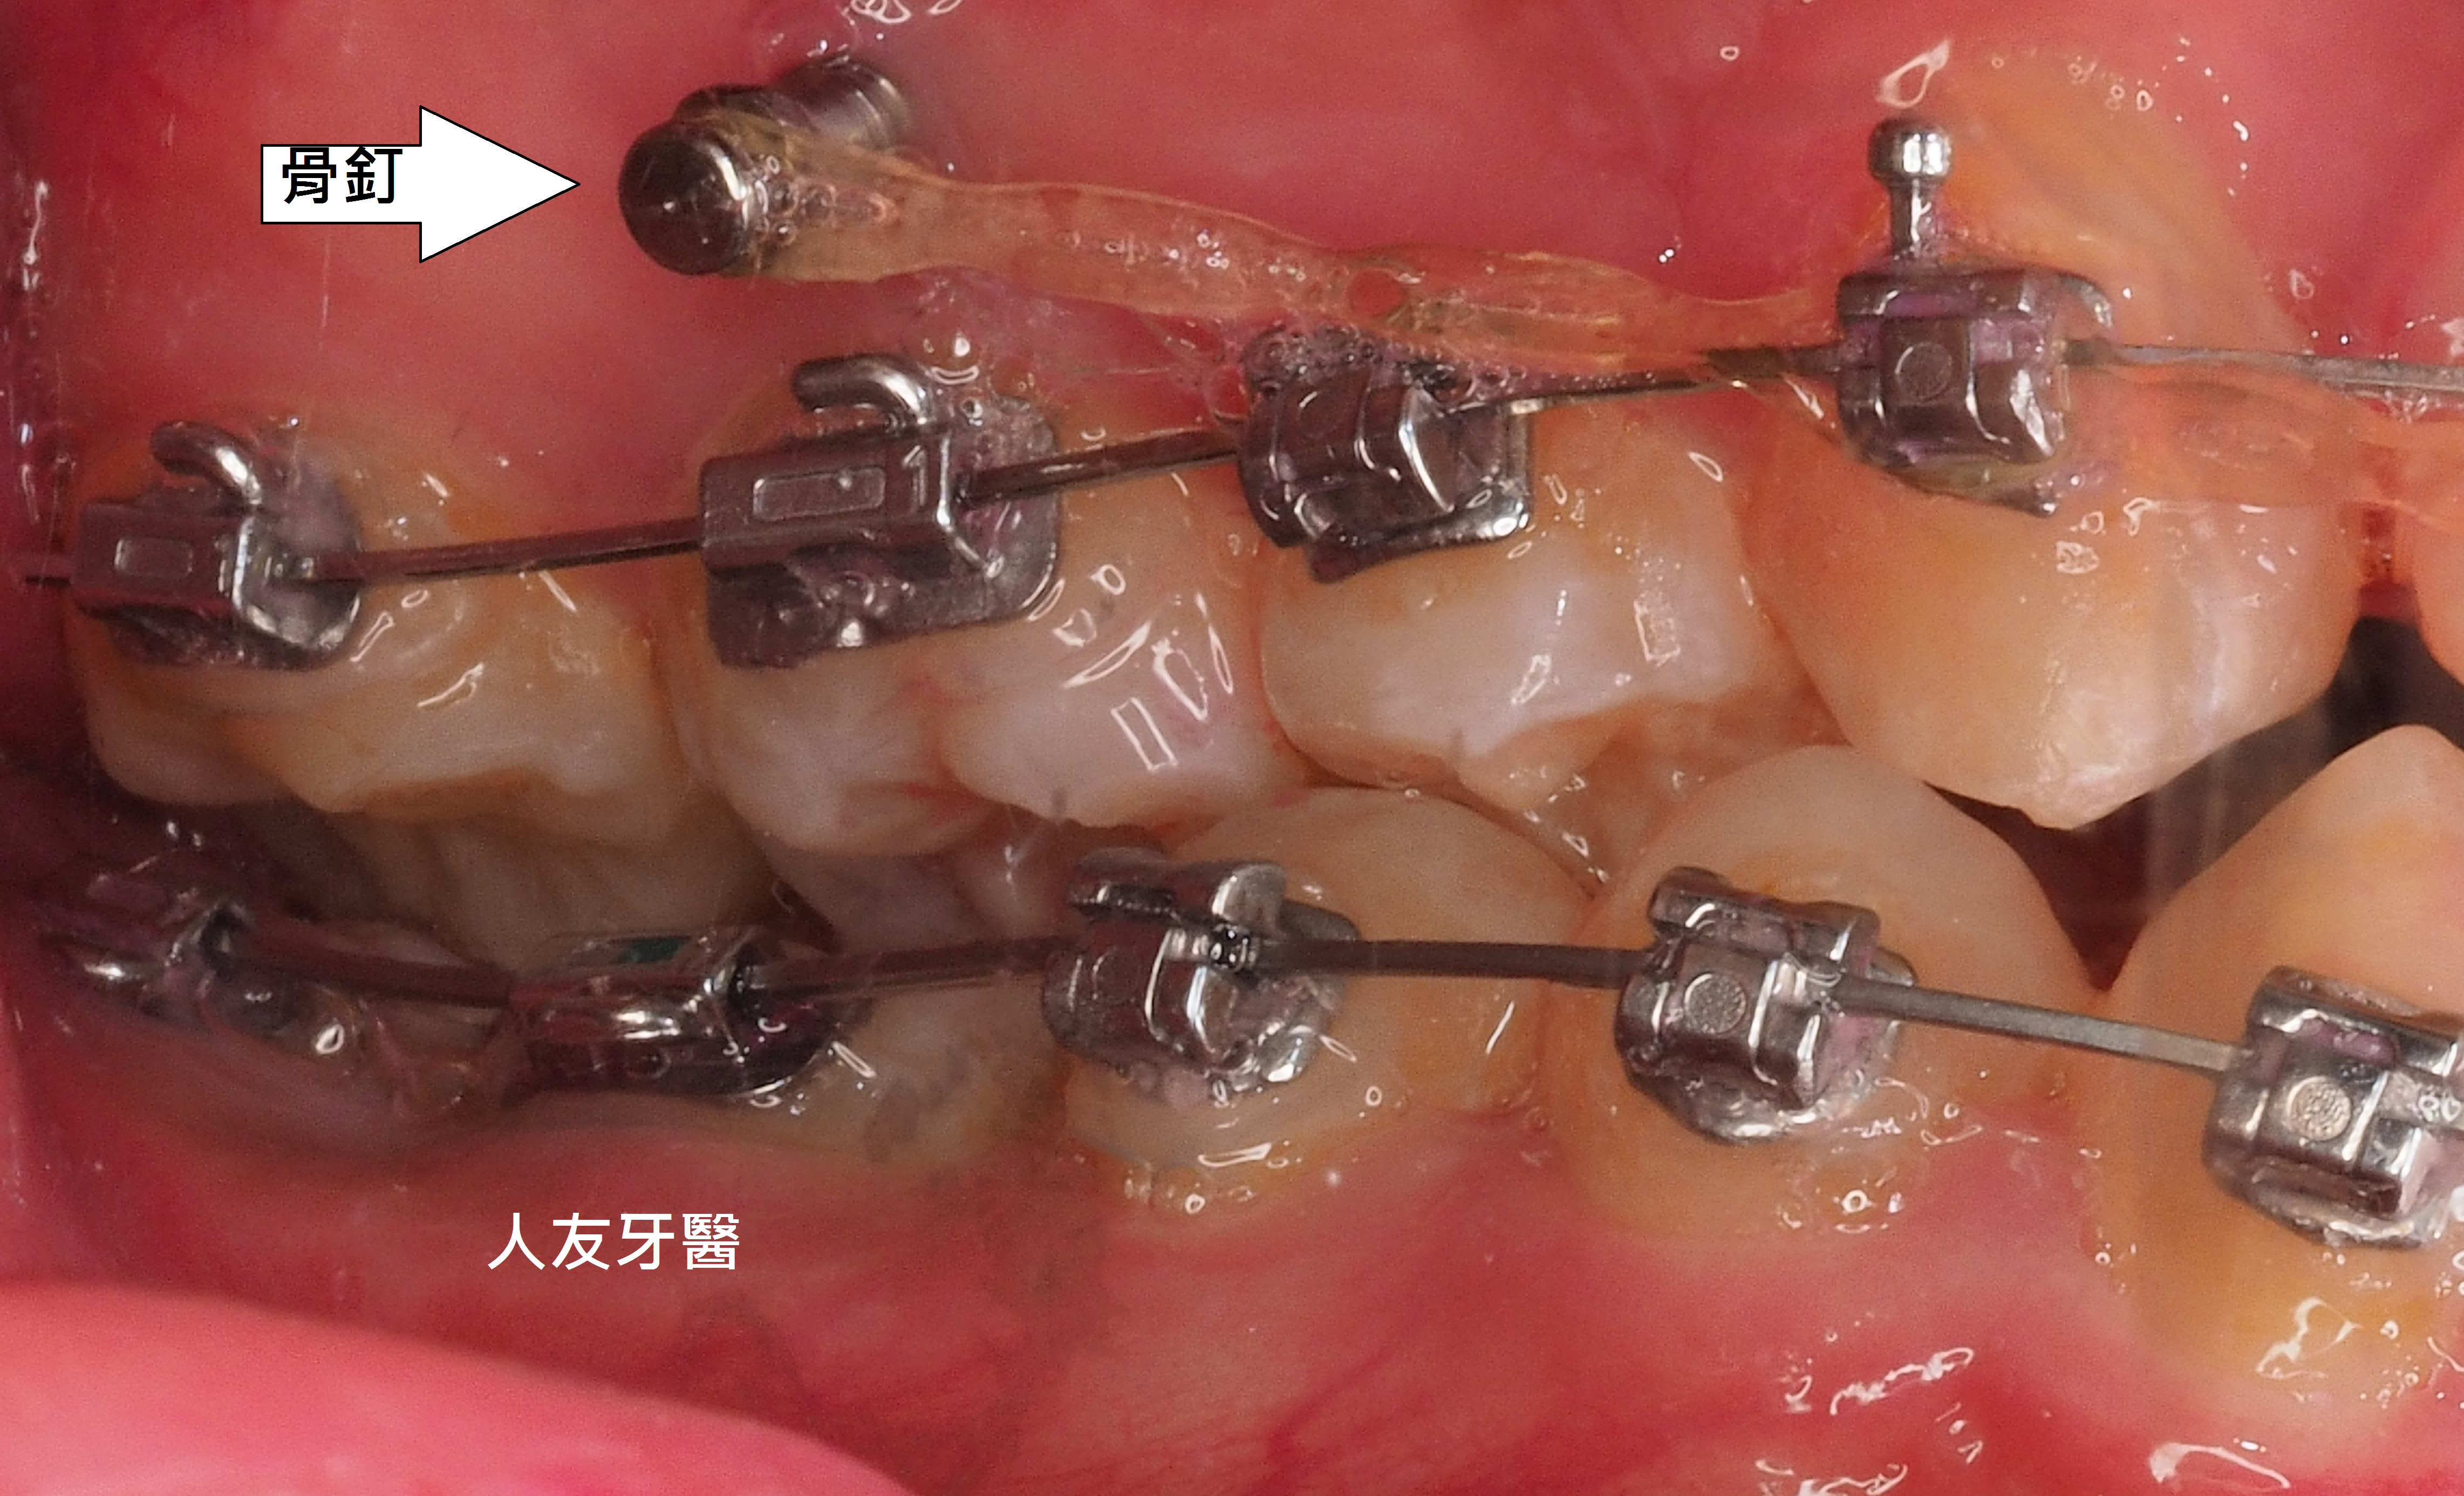

患者牙齒凌亂虎牙外暴大大影響外觀,並造成清潔不易、蛀牙、牙齦發炎等問題,透過醫師矯正評估分析建議矯正計畫內容包含拔牙、放置迷你螺絲(骨釘)等步驟,將原本凌亂外暴的虎牙歸位,改善咬合使發音更清晰,咀嚼效率更好,大幅改善清潔困擾,使日常刷牙及使用牙線清鬆有效率。

3.拔牙與骨釘:為騰出空間進行矯正,需要拔牙;骨釘用於輔助移動牙齒,初期可能會有異物感,但通常很快能適應。(下兩圖)

拔牙後放骨釘關閉空間原理與優點:

1.骨釘是植入在骨頭中的支撐點,提供穩定的錨定力量,確保牙齒移動的方向不受影響。

2.傳統矯正中移動牙齒可能造成其他牙齒跟著移動,使用骨釘可以精準控制牙齒的移動方向,讓拔牙後的縫隙能有效且正確地關閉。

3.骨釘可以大幅提升牙齒移動的效率,可能縮短矯正療程時間。

4.除了關閉拔牙空間,骨釘還能應用於骨性暴牙、嚴重深咬等情況,讓治療範圍更廣。